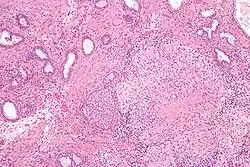

Micrograph showing granulomatous inflammation of bladder neck tissue due to Bacillus Calmette-Guérin used to treat bladder cancer, H&E stain

BCG has been one of the most successful immunotherapies.[27] BCG vaccine has been the "standard of care for patients with bladder cancer (NMIBC)" since 1977.[27][28] By 2014 there were more than eight different considered biosimilar agents or strains used for the treatment of non–muscle-invasive bladder cancer (NMIBC).[27] [28]

• BCG is used in the treatment of superficial forms of bladder cancer. Since the late 1970s, evidence has become available that instillation of BCG into the bladder is an effective form of immunotherapy in this disease.[29] While the mechanism is unclear, it appears a local immune reaction is mounted against the tumor. Immunotherapy with BCG prevents recurrence in up to 67% of cases of superficial bladder cancer.